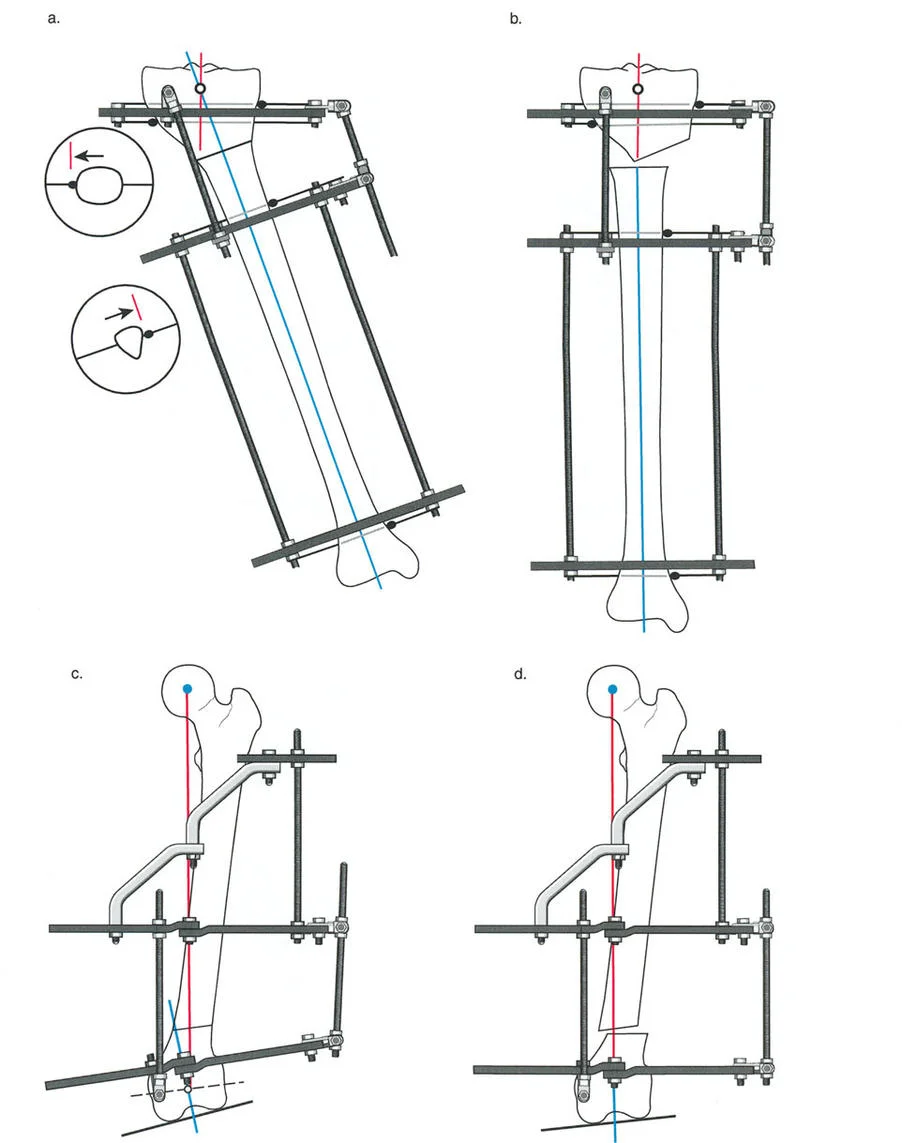

المفصلات القريبة من المفصل وقواعد قطع العظم (Osteotomy Rules)

عند التعامل مع التشوهات الواقعة بالقرب من خط المفصل - مثل التقوس الشديد في الجزء العلوي من الساق (مرض بلونت) أو التشوه الفحجي في الجزء السفلي من عظم الفخذ - يصبح وضع الجهاز مقيدًا هندسيًا. إن المتطلبات البيولوجية للحفاظ على كبسولة المفصل، وتجنب وضع الأسلاك داخل المفصل، ومنع التهاب المفاصل القيحي، غالبًا ما تجبر الجراح على وضع الحلقة المرجعية على مستوى مختلف تمامًا عن مركز دوران الانحراف (CORA) الفعلي.

تحدي مركز دوران الانحراف (CORA) القريب من المفصل

لمطابقة مفصلة المثبت الخارجي مع المستوى الدقيق لمركز دوران الانحراف (CORA)، يجب غالبًا بناء المفصلة فوق أو تحت مستوى الحلقة الفعلية. يُعرف هذا في مبادئ بالي باسم تجميع المفصلة القريبة من المفصل (juxta-articular hinge assembly).

إذا كان مركز دوران الانحراف (CORA) يقع بالقرب من خط المفصل، فإن وضع حلقة إليزاروف القياسية عند هذا المستوى بالضبط مستحيل دون انتهاك مساحة المفصل أو شد الهياكل الكبسولية الحيوية. لذلك، يتم تثبيت الحلقة المرجعية بالعظم الكثيف أو العظم الطويل المتاح، ويتم بناء آلية المفصلة باستخدام قضبان ملولبة، ولوحات توصيل، ودعامات. ثم يتم "إنزالها" (أو رفعها) لتتطابق تمامًا مع مركز دوران الانحراف (CORA) الهندسي الحقيقي.

قواعد بالي لقطع العظم (Osteotomy Rules) في وضع الأجهزة

فهم قواعد بالي لقطع العظم أمر لا غنى عنه لتخطيط الإطار:

- قاعدة قطع العظم 1: عندما يمر قطع العظم ومحور تصحيح الانحراف (ACA) كلاهما عبر مركز دوران الانحراف (CORA)، فإن نهايات العظم ستنحرف دون ترجمة (انزياح). يتم استعادة المحور الميكانيكي، وتظل نهايات العظم متقاربة تمامًا، مما يخلق تصحيحًا كلاسيكيًا "إسفينيًا مفتوحًا" أو "إسفينيًا مغلقًا".

- قاعدة قطع العظم 2: عندما يمر محور تصحيح الانحراف (ACA) عبر مركز دوران الانحراف (CORA)، ولكن يتم إجراء قطع العظم على مستوى مختلف (غالبًا بسبب ضعف جودة العظم عند CORA أو مشاكل في الجلد)، فإن نهايات العظم ستنحرف وتخضع لترجمة محسوبة ومقصودة لإعادة محاذاة المحور الميكانيكي.

- قاعدة قطع العظم 3: (للاكمال) عندما يمر قطع العظم عبر مركز دوران الانحراف (CORA)، ولكن يتم وضع محور تصحيح الانحراف (ACA) خارج CORA، سيتم إنشاء تشوه ترجمة جديد، وهو خطأ شائع في وضع المفصلات غير المخطط له جيدًا.

في المنشآت القريبة من المفصل، غالبًا ما نعتمد على قاعدة قطع العظم 2. نظرًا لأنه لا يمكننا قطع العظم بأمان عند خط المفصل تمامًا (مركز دوران الانحراف CORA)، فإننا نقطع العظم في مستوى أدنى في منطقة الميتافيسيس. بعد تحقيق التصحيح الزاوي عبر المفصلات (محور تصحيح الانحراف ACA)، يتم إعادة محاذاة خطوط المحور الميكانيكي بشكل مثالي، ولكن نهايات العظم في موقع قطع العظم تتحرك بالنسبة لبعضها البعض.